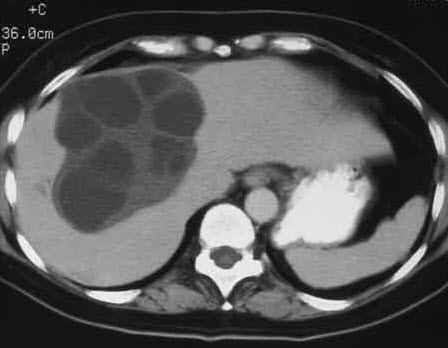

Laboratory studies. White blood cell (WBC) count, 5100/µL, with 60% polymorphonuclear leukocytes, 32% lymphocytes, 4% eosinophils, 4% monocytes. Hemoglobin level, 13.6 g/dL; platelet count, 200,000/µL; erythrocyte sedimentation rate, 8 mm/h. Urinalysis reveals no protein and no bilirubin; WBC count, 2 per high-power field; no red blood cells. Blood glucose level, 84 mg/dL. Blood urea nitrogen level, 18 mg/dL; creatinine, 0.8 mg/dL; serum sodium, 138 mEq/L; potassium, 3.7 mEq/L; chloride, 100 mEq/L; bicarbonate, 22 mEq/L; total bilirubin, 1 mg/dL; conjugated bilirubin, 0.8 mg/dL. Total protein, 8 g/dL; albumin, 4.2 g/dL; globulin, 3.8 g/dL; alkaline phosphatase, 200 U/L; aspartate aminotransferase, 21 U/L; alanine aminotransferase, 20 U/L. Ultrasonography reveals a large cystic lesion in the right lobe of the liver.

An abdominal CT scan is ordered.

In view of the clinical picture and ultrasonographic and CT findings, what is the most likely diagnosis?

Ultrasonography is the procedure of choice because it is safe, noninvasive, and relatively inexpensive. Typical findings consist of solitary or multiple round or spherical 1- to 15-cm cystic lesions. Cysts filled with hydatid fluid are centrally anechoic with well-defined outer contours. Internal septations are characteristic of multiple daughter cysts within a large mother cyst.

CT and MRI permit better documentation of site, size, and structure, particularly of small cysts; monitoring of lesions during chemotherapy; the evolution of calcification; and detection of postoperative recurrence of cystic lesions.